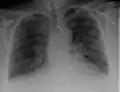

Chest X-rays are frequently used to aid in the diagnosis of CHF. In a person who is compensated, this may show cardiomegaly (visible enlargement of the heart), quantified as the cardiothoracic ratio (proportion of the heart size to the chest). In left ventricular failure, evidence may exist of vascular redistribution (upper lobe blood diversion or cephalization), Kerley lines, cuffing of the areas around the bronchi, and interstitial edema. Ultrasound of the lung may also detect Kerley lines.[72]

Congestive heart failure with small bilateral effusions